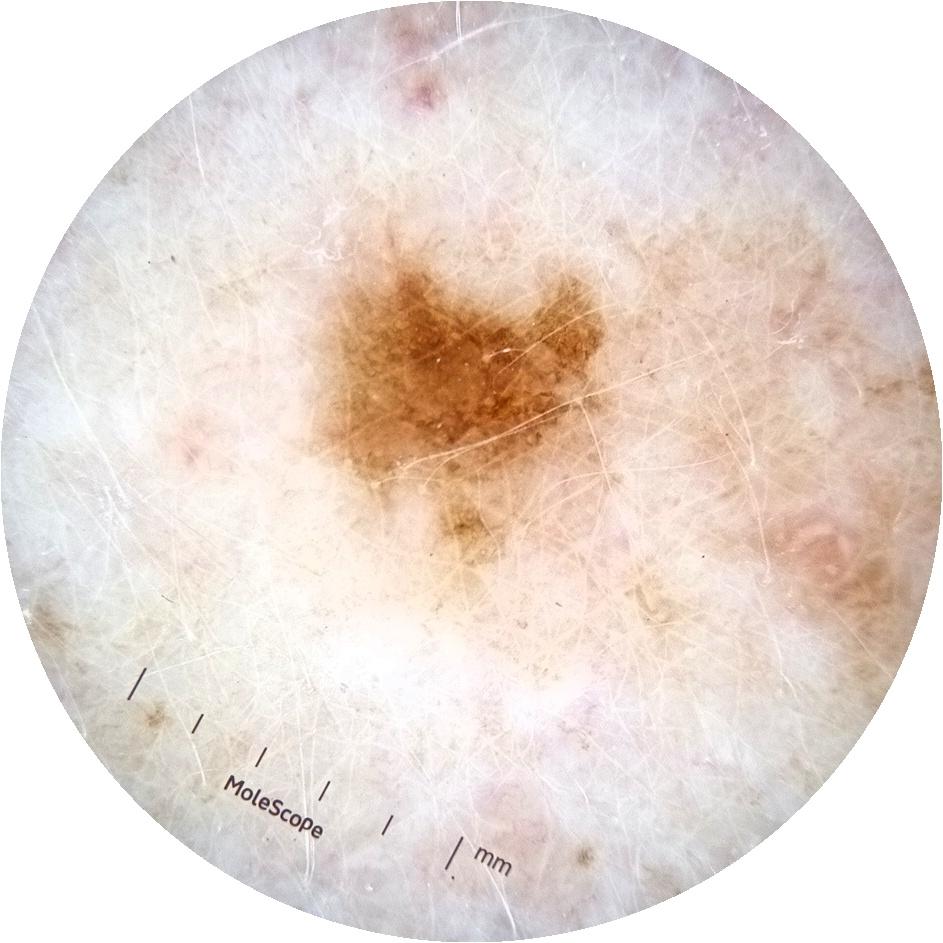

ISIC_3754278

MEL-SELF Trial, https://www.sydney.edu.au/medicine-health/our-research/research-centres/melself-project.html

Clinical

Field Value

acquisition_day 135

age_approx 65

anatom_site_1 Upper extremity

anatom_site_general upper extremity

diagnosis_1 Benign

diagnosis_confirm_type single image expert consensus

image_type dermoscopic